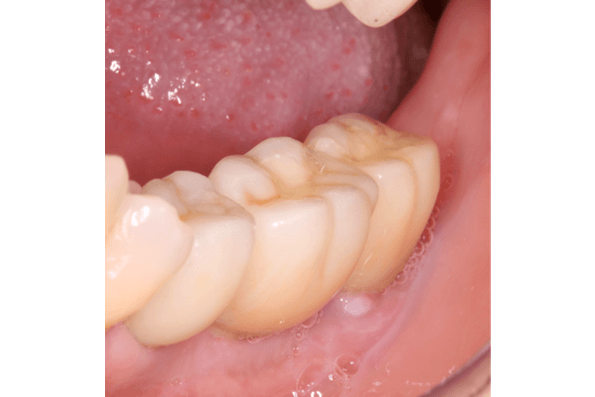

Próteses Fixa sobre implante

É utilizada para substituir ,através de implantes intra-ósseo, dentes já condenados que foram, ou ainda precisam ser extraídos. É a melhor opção capaz de restabelecer função mastigatória, conforto e estética, seja em casos de reabilitação de um único dente ou até de uma arcada dentária inteira (protocolo). As próteses sobre implante podem ser produzidas com diversos materiais, e esta escolha se torna fundamental para um resultado estético favorável.